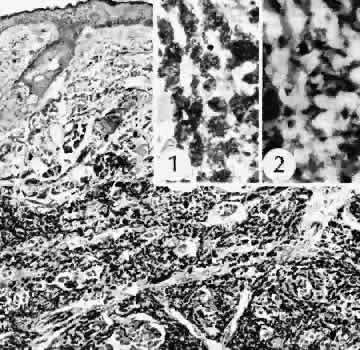

Fig. 28. A case of lens capsular rupture during intracapsular cataract extraction. On postoperative day 1 (inset 1), there was considerable retention of lens capsular material nearly obscuring the anterior chamber. By postoperative day 14 (inset 2), considerable clearing of debris has occurred. At 2 months following surgery (inset 3), the anterior chamber was nearly clear. The clearing of the debris was through the action of macrophages ingesting the cortical debris and exiting the eye through the trabecular apparatus. Macrophages filled with lens cortical material from a different case are seen in the main figure. (Periodic acid-Schiff stain; × 700.) (Yanoff M, Scheie HG: Cytology of human lens aspirate. Its relationship to phacolytic glaucoma and phacoanaphylactic endophthalmitis. Arch Ophthalmol 80:166–170, 1968.)